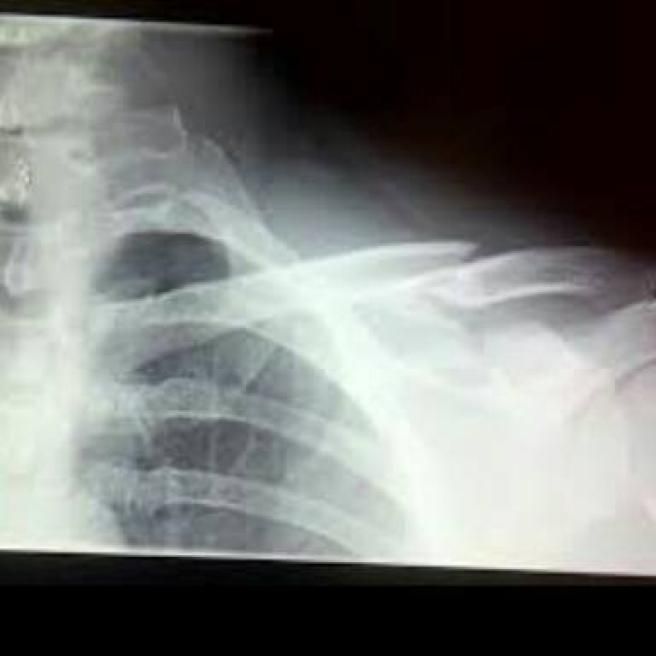

Joe Bastianich cade sullo Zoncolan e si frattura la clavicola e due costole